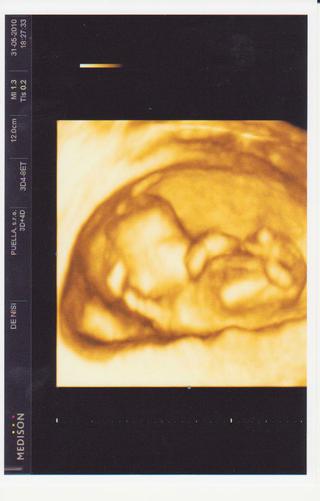

jani a pekne miminko, cela maminka...

@koblizek.janinka janinko jojo mrkala jsem je to nadherna fotečka 🙂